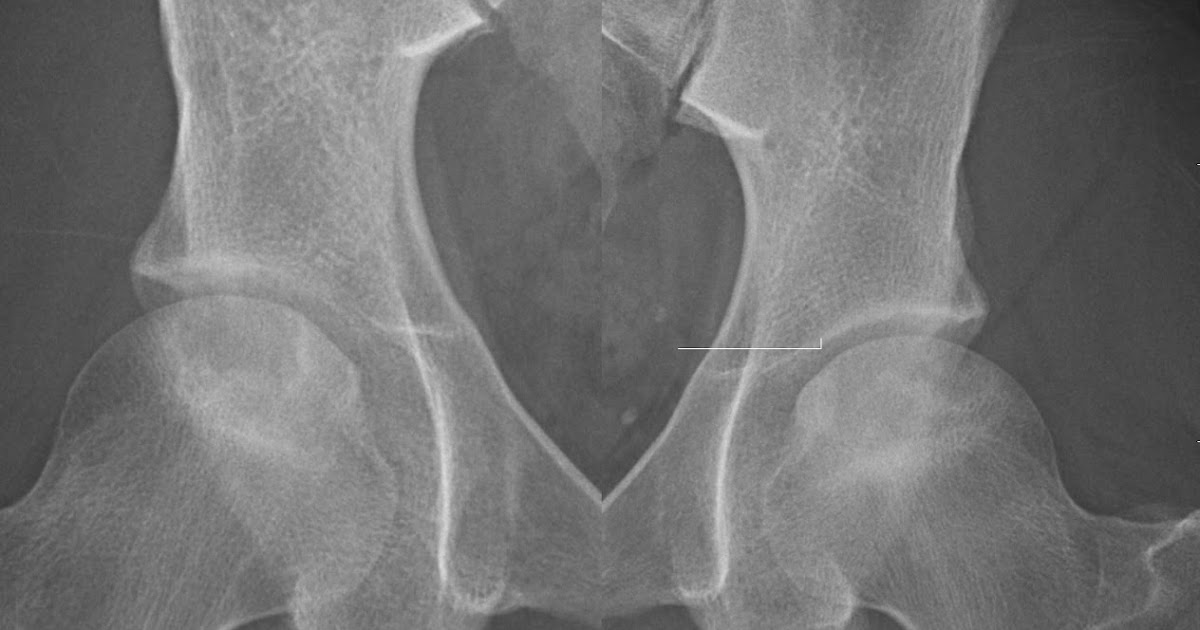

Bilateral AVN Radiology, Case Avn Names Radiology Hip osteonecrosis, also known as avascular necrosis of the hip, represents a condition caused by reduced blood flow to the femoral head secondary to a variety of risk factors such as. There are numerous causes of avascular necrosis (avn), which is at its most basic definition when blood flow to a bone is. Avascualr necrosis (avn), also called osteonecrosis or. Avn Names Radiology.

Bilateral Avascular Necrosis (AVN) of the Femoral Heads radRounds Avn Names Radiology Osteonecroses) is a generic term referring to the ischaemic death of the constituents of bone. Hip osteonecrosis, also known as avascular necrosis of the hip, represents a condition caused by reduced blood flow to the femoral head secondary to a variety of risk factors such as. Avascular necrosis (avn), also known as osteonecrosis, is most common in the femoral head.. Avn Names Radiology.